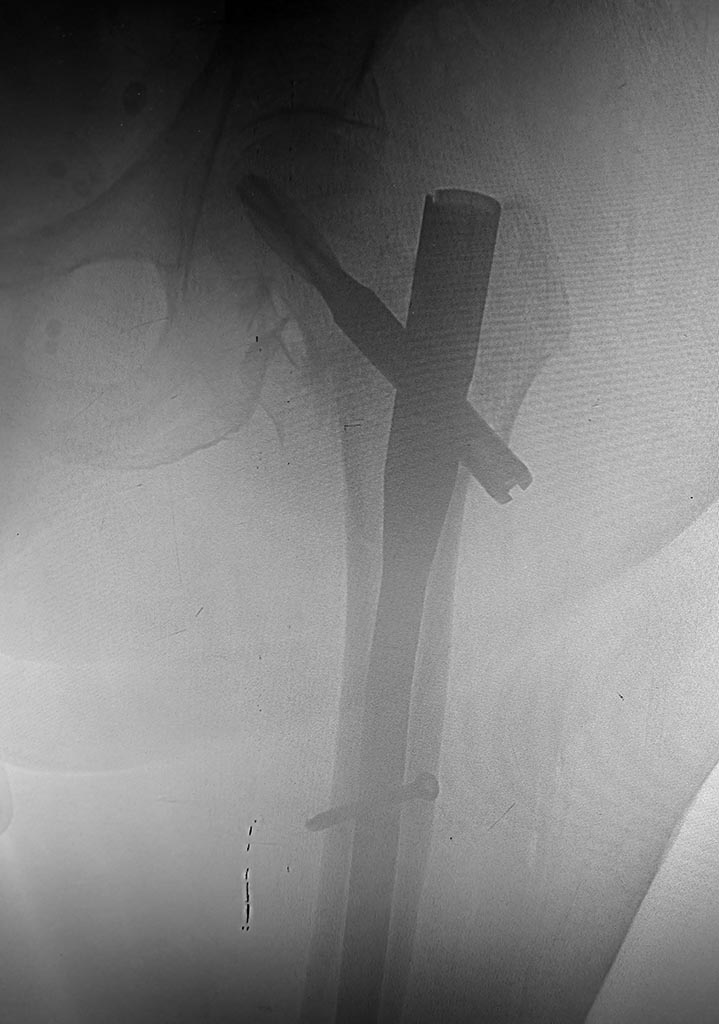

Использовали полер-спицы для форммрования канала и винт Шанца для удержания отломка б.вертела при заведении гвоздя.

еще проекция